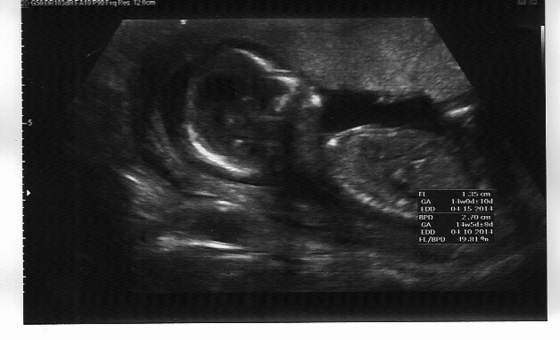

To teraz wczorajsza sesja zdjęciowa